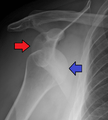

Lightbulb sign indicative of posterior shoulder dislocation shown on the left. On the right, the same shoulder after reduction.